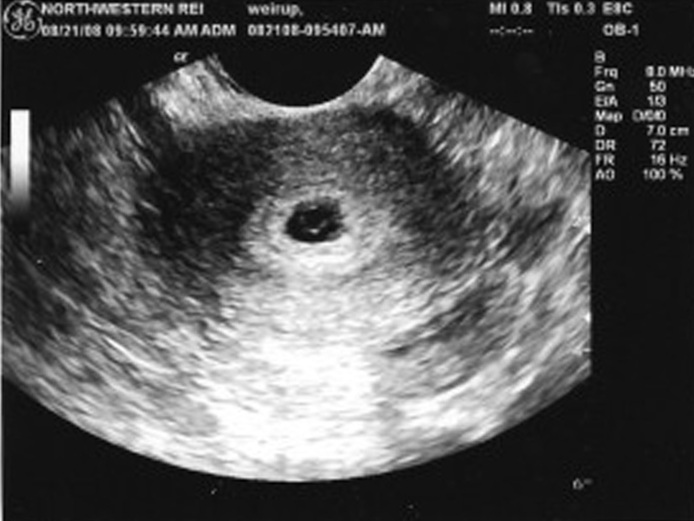

На первом УЗ-исследовании подтверждают наличие беременности, устанавливают расположение зародыша, частоту его сердцебиения, просматривают плодное яйцо (их может быть несколько) и точно определяют срок беременности.

Отличительная особенность оборудования в том, что оно показывает плодное яйцо даже на первой неделе задержки. Однако это не гарантирует наличия беременности. Образование может не содержать эмбрион, тогда УЗИ покажет простое клеточное скопление.

Получить точный ответ получится только через 4 недели задержки — тогда плод достаточно сформирован для проведения исследования через ультразвуковой аппарат.

Первое УЗИ при беременности